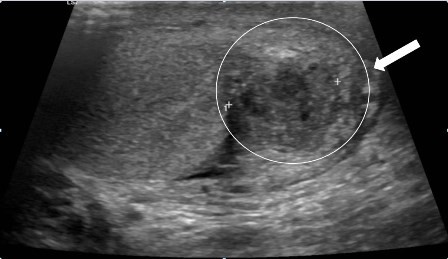

Siêu âm tinh hoàn bao gồm cả siêu âm Doppler mạch là cần thiết để đánh giá tổn thương, đồng thời loại trừ các trường hợp có áp xe, khối u, cũng như xoắn tinh hoàn.

Hình 1. Hình ảnh viêm mào tinh hoàn trên siêu âm Dopler